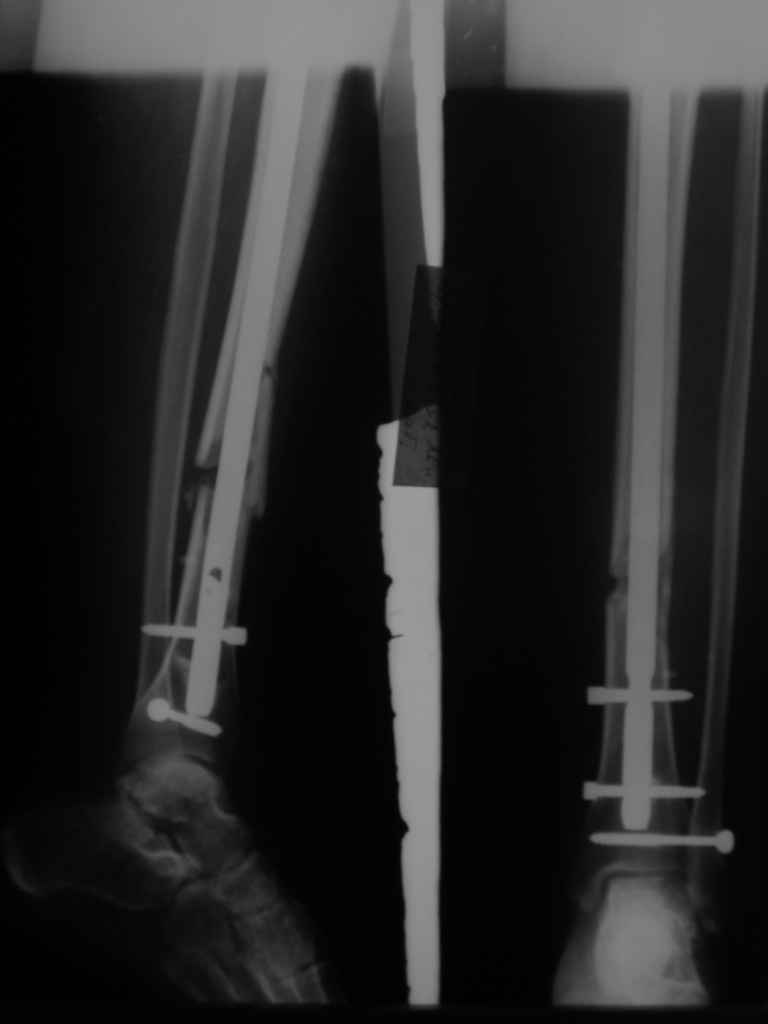

"Ходит с ограниченной нагрузкой на ногу. Направлен из травмпункта по поводу оставшегося смещения отломков. У нас разделилось мнение коллег по вопросу - есть ли необходимость в закрытом интрамедуллярном реостеосинтезе с исправлением оси или только ограничиться динамизацией гвоздя"

Техника введения штифта в дистальные переломы голени отличается от введения в c/3 диафиз. В дистальном отделе штифт надо ввести поглубже и блокировку внизу сделать на все возможные дистальные отверстия. В верхней части короткий штифт создает запас для будущей динамизации.

Одним из идеальных штифтом для лечения дистальных переломов голени является от Synthes Expert Nail, где имеется 4 возможные отверстия для дистальной блокировки, которые в различных направлениях создают дополнительную стабильность.

На снимке сохранен небольшой вальгус, но имеется нормальная аппозиция медиального кортикального слоя и поэтому трудно согласится что здесь имеется неправильно фиксированный перелом. Для идеального сопоставления таких косых переломов надо открывать фокус травмы, но тогда меняется философия фиксации.

Навряд ли рискованные манипуляции в фокусе травмы или ре-остеосинтез улучшит результат кроме рентгенологической картины.

Для предупреждения осложнении можно оставить как есть, потому что всего месяц с момента операции и не видно признаков несостоятельности остеосинтеза.

Отсутствие болей показания к нагрузке и после восстановления движения в суставе через пару-три недели можно сделать динамизацию. За редким исключением, обычно такие “неправильно фиксированные” переломы сростаются в срок.